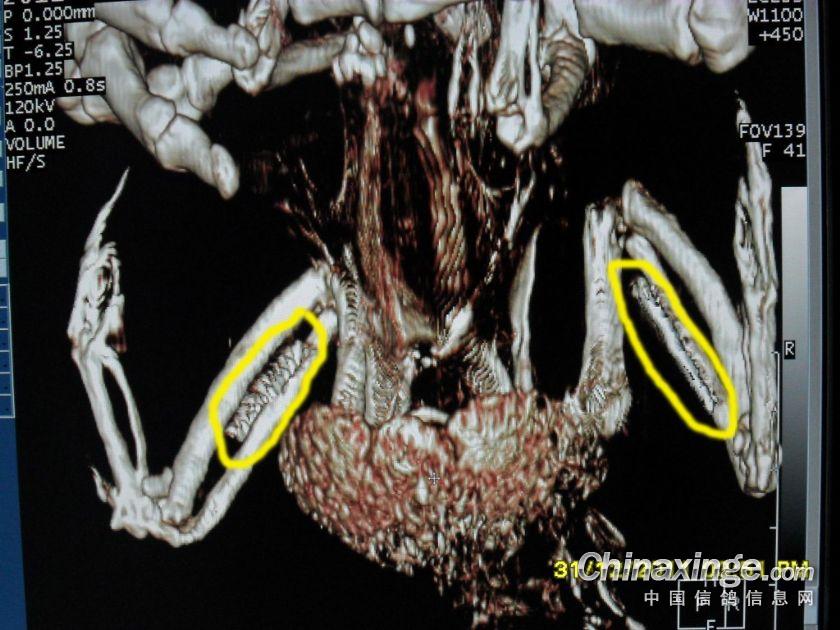

双侧翅膀的金属物

不同角度的金属物图片